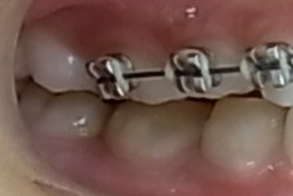

その後、下顎にも矯正装置を装着して歯並びを綺麗にしていきます。

その後、MEAW(マルチループ)と顎間ゴムを24時間利用する事で受け口(下顎前突)と歯並びを改善していきます。

その後、矯正装置を除去していきます。

治療前はAngleⅢ級でしたが歯(第一小臼歯)を抜く事無くAngleⅠ級に改善しています。つまり、矯正治療の最終目標である個性正常咬合になっています。